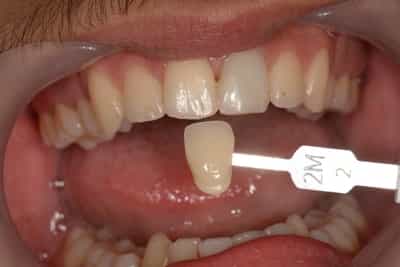

Souvent, il sera plus judicieux de réaliser un éclaircissement avant un travail prothétique, ou des composites antérieurs, car les techniques d’éclaircissements ne sont pas actives sur les céramiques ou les composites.

Situation Initiale

Etude du cas et proposition